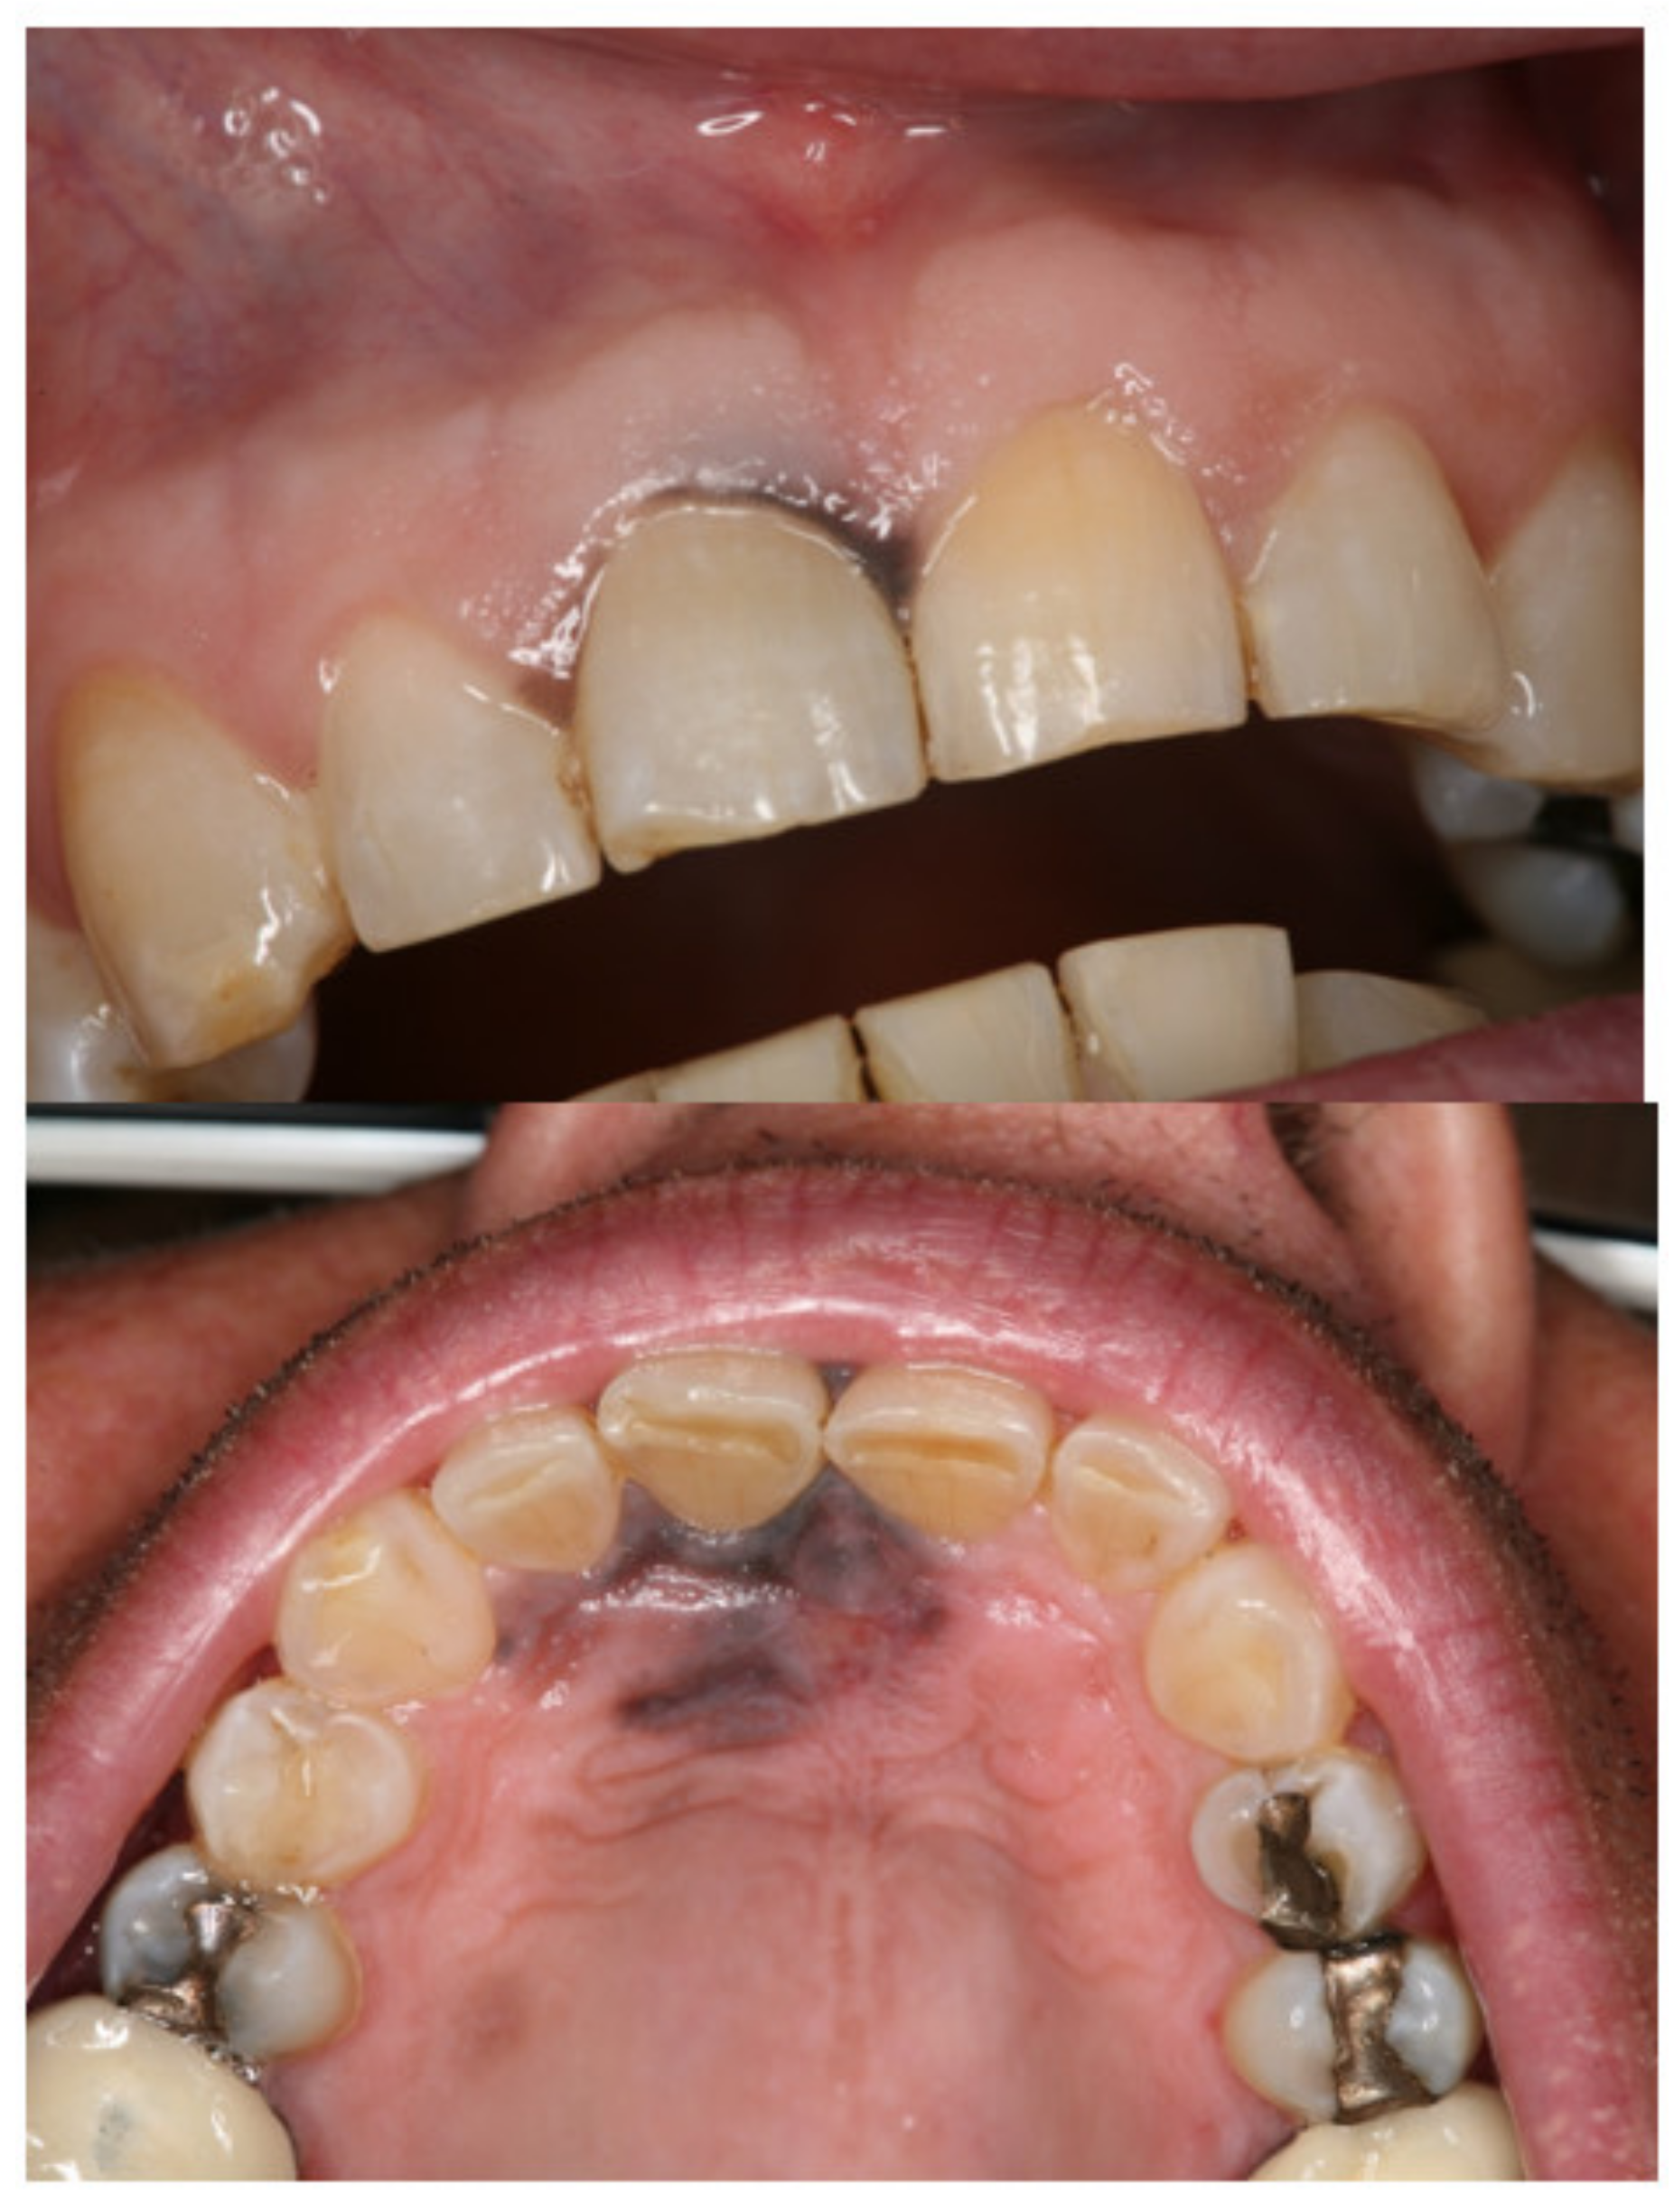

2. Case Report